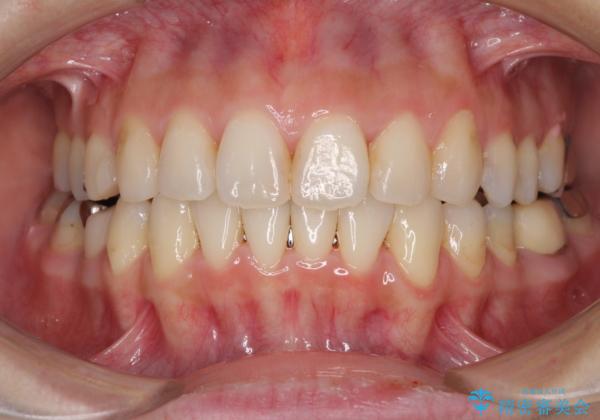

上顎骨拡大を併用したインビザライン矯正

- 上下のデコボコと奥歯の咬みにくさを気にして来院された患者様です。

上顎骨の幅が下顎骨よりも小さいので、拡大装置により骨幅を広げて上下関係を改善し、その後インビザラインにて歯並びを整えることとしました。

上下の骨幅を改善したことで、スムーズに歯列矯正を行うことができました。

矯正治療中に近医で銀歯を外す治療を開始したため、治療後に奥歯の咬み合わせが不十分ですが(こちらは近医での治療により改善するとのこと)、歯列と咬み合わせが改善され、患者様には大変満足していただきました。